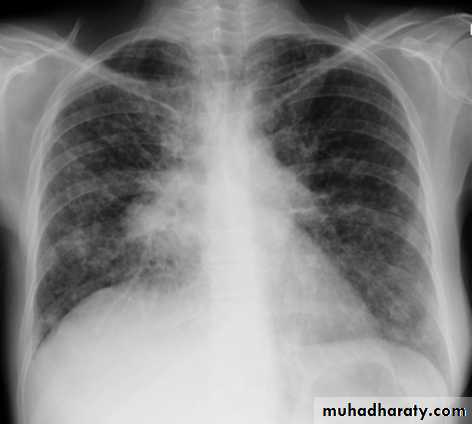

Lobular consolidation ( broncho pneumonia )

Very important to consider that pulmonary edema in normal sized heart have close similar appearance to broncho pneumonia

The important Golden Key differentiation is the cardiac size being enlarged in pulmonary edema .

36.lobuler consolidation (lobular pneumonia )37.discussion